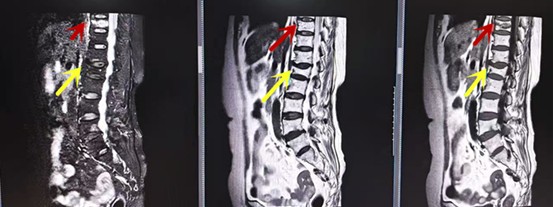

箭頭提示腰椎管內(nèi)腫瘤

紅色箭頭提示新鮮骨折,黃色箭頭提示陳舊性骨折